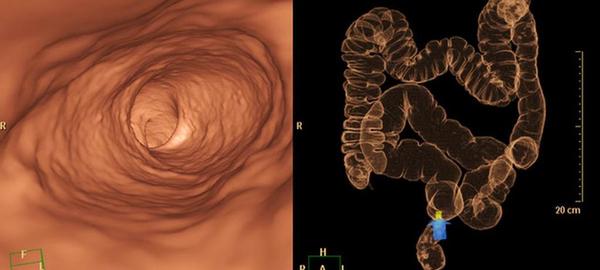

Coloscopie virtuelle : à qui s'adresse ce scanner non invasif ?

La coloscopie virtuelle ou coloscopie par scanner permet de visualiser le côlon et de détecter d'éventuels polypes précancéreux. L’examen est plus rapide qu'une coloscopie traditionnelle et ne requiert pas d’anesthésie.